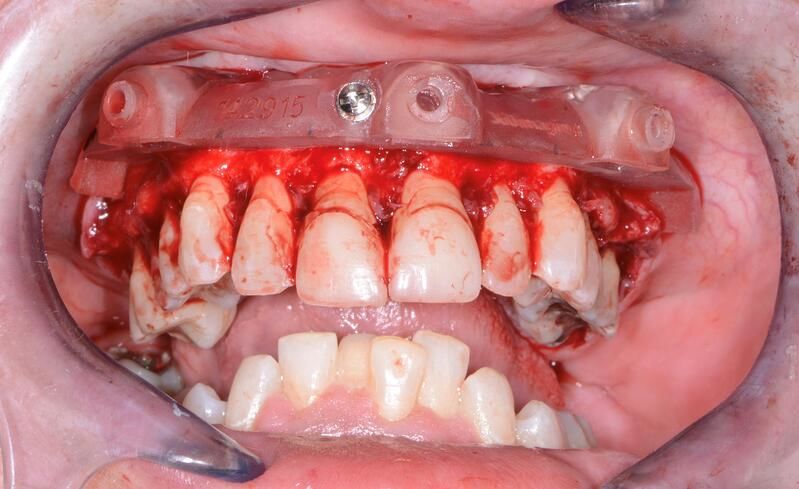

術(shù)中過(guò)程